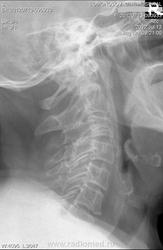

Старый компрессионник в нижне-грудном - ерунда, но боли давать может. Дегенеративные изменения. В шейном что-то ничего страшного и не нашла... А вот в верхне-грудном отсутствует передний контур 2-х позвонков и часть верхней замыкательной пластинки спереди... Может, проекционное, но перебдеть не помешает, наверное. Хотя перебдёж - моя специфика, чаще ничего интересного не находится).

А старый перелом по одной боковой получается в Th10

В С3,6 смущают полосы просветлений - проекционные? от чего?

Как пишут рентгеновские корифеи травматический перелом позвонков происходит за счёт верхней пластинки, а здесь повреждена нижняя. Может быть и мтс.